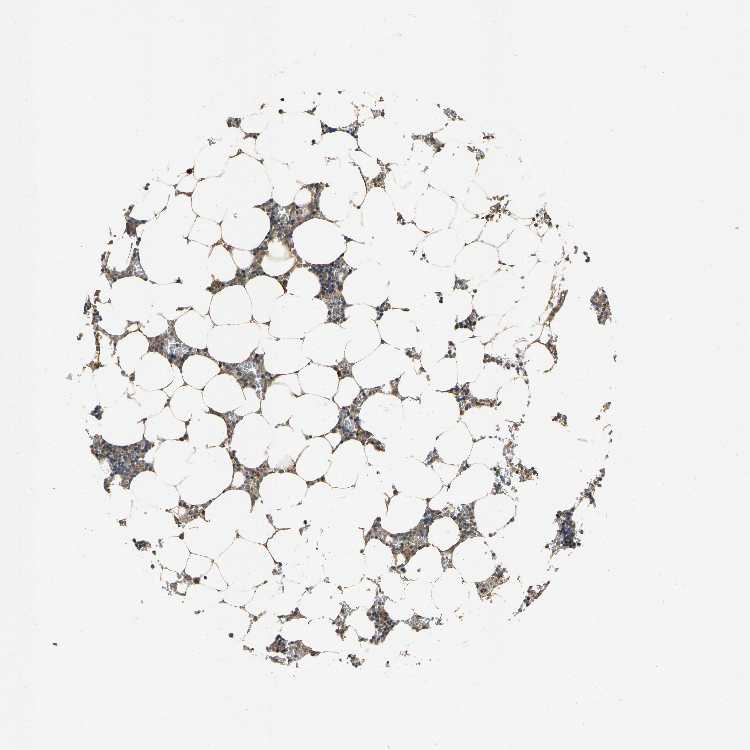

BONE MARROW - Antibody stainingi

Antibody staining in the annotated cell types in the current human tissue is reported as not detected, low, medium, or high, based on conventional immunohistochemistry profiling in selected tissues. This score is based on the combination of the staining intensity and fraction of stained cells.

Each image is clickable and will lead to virtual microscopy that enables deeper exploration of all samples and also displays staining intensity scores, fraction scores and subcellular localization as well as patient and tissue information for each sample.

Antibody HPA020397Antibody HPA024150

Hematopoietic cells MediumHigh